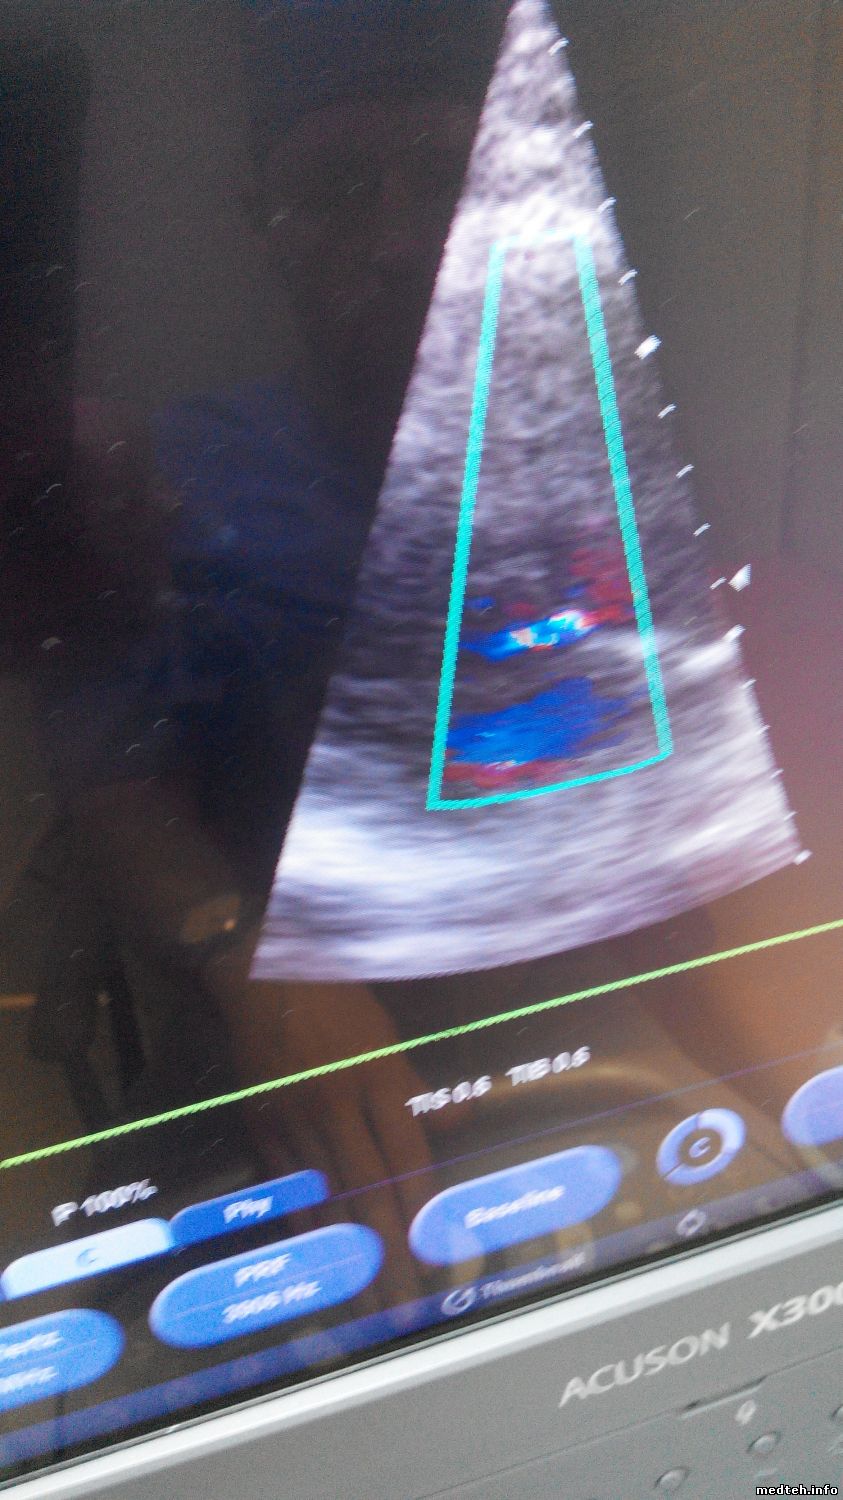

Итог: С подменными от моего не исправного УЗИ результата не дало, мои 2 секторных датчика Р4-2 и Р8-4 на том аппарате работают хорошо!!!!!!!!!! unknown

А на моём УЗИ, эти же датчики, при сердечном кровотоке ШУМЯТ!!!! ПОМЕХИ и прочую паразитивную гадость показывают!!!!!!!!!!!

Вот фото с помехами, я настроил чувствительность так, что я даже не дотрагиваюсь до них, а картинка КОШМАРНАЯ!!!!!!

А вот как ведут эти же датчики на исправном УЗИ аппарате:

Без помех- строго по делу!!!